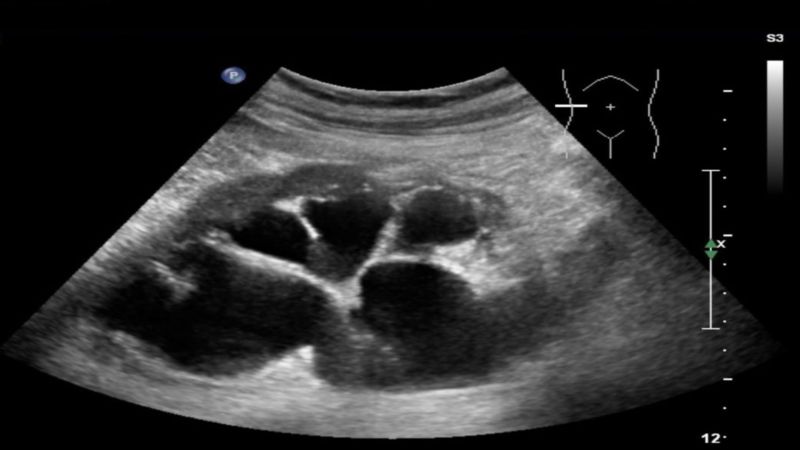

- Siêu âm: Xét nghiệm này sẽ sử dụng sóng âm thanh để tạo ra hình ảnh toàn bộ đường tiết niệu của người bệnh, bao gồm cả thận và bàng quang. Ngoài ra, siêu âm thai nhi có thể phát hiện những dấu hiệu của trào ngược bàng quang niệu quản khi mang thai như thận ứ nước.

Siêu âm sẽ giúp phát hiện tình trạng thận ứ nước